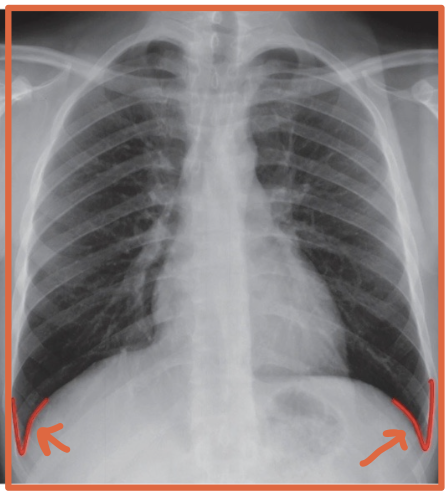

What is a costophrenic angle/sulcus?

The sharp recess where the diaphragm meets the chest wall

Why are the costophrenic angles/sulcus clinically important?

Pleural fluid collects there